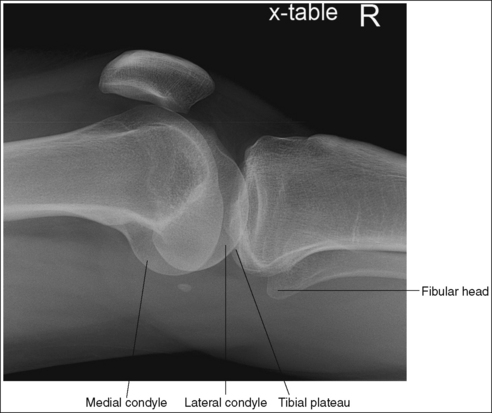

• Supine (cross-table) lateromedial knee projection. When a lateral knee projection is taken using a lateromedial projection, with a horizontal central ray, the cephalad central ray angulation described above is not required, as long as the patient's femoral inclination is not reduced or increased by the distal femur being shifted too laterally or medially, respectively. Images 70 and 71 are cross-table lateral knee projections that demonstrate a femoral condyle within the knee joint space because of poor femoral positioning. Image 70 demonstrates the lateral condyle in the joint space and image 71 demonstrates the medial condyle. When such images are produced, view how far the fibular head is positioned from the tibial plateau. When the distal surfaces of the femoral condyles are accurately superimposed, the fibular head will be positioned about 0.5 inch (1.25 cm) from the tibial plateau. If the central ray (CR) is rotated distally or the leg adducted (moved too medially) for a lateromedial projection of the knee, the lateral condyle will be projected distal to the medial condyle and the fibular head will move farther than 0.5 inch (1.25 cm) from the tibial plateau (see Image 70). If the CR is rotated proximally or the leg abducted (moved too laterally) for a lateromedial projection of the knee, the lateral condyle will be projected proximal to the medial condyle and the fibular head will move closer than 0.5 inch (1.25 cm) from the tibial plateau (see Image 71).